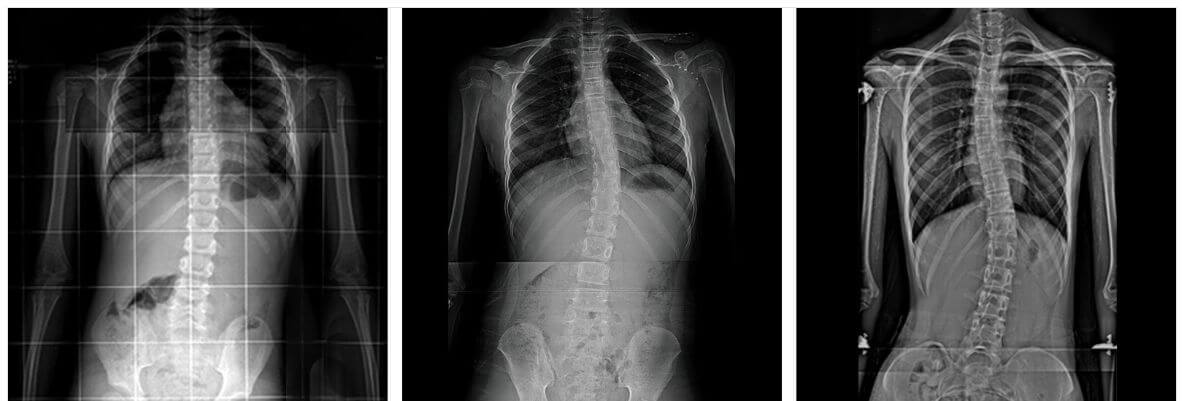

우리가 흔히 척추측만증으로 부르는 척추옆굽음증은 척추의 형태가 앞, 뒤, 좌, 우 혹은 복합형으로 틀어지고 휘어진 형태를 말합니다.

X-ray검사를 하면 척추뼈의 기형을 비교적 쉽게 발견할 수 있습니다.

측만증의 심한 정도는 각도로 표시하며, 이 각도의 정확한 명칭은 콥스각(Cobb's angle)이라 합니다. 이 각도가 몇 도인지 알아야 치료를 결정할 수 있습니다.

보통 척추가 10도 이내로 휘었을 때는 측만증이라 하지 않는데, 이는 일시적인 통증이 오거나 측만증이 없는 상태에서도 척추가 보통 10도 정도 휠 수 있기 때문입니다.

25도가 넘으로면 외관상의 변화가 나타나고, 45도 이상이면 수술적 치료대상이 됩니다.